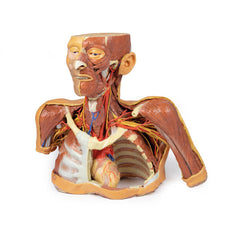

This 3D model is a midsagittal hemisection through a whole brain, preserving the right side anatomy and deep brain

structures and spaces visible in the midline. In lateral view, the right cerebral and cerebellar hemispheres are

covered in the arachnoid mater. In the midline view, the brain regions from the cerebrum to the medulla oblongata

are preserved. Centrally, the third ventricle is opened, with an intact septum pellucidum superiorly positioned and

obscuring the lateral ventricles within the cerebral hemisphere. On the inferior margin of the third ventricle both

the right mamillary body and right optic tract can be observed, whereas posteriorly the cerebral aqueduct can be

observed extending across the midbrain between the tectum and tegmentum towards the fourth ventricle (between the

cerebellum and pons). The cerebellum is separated from the occipital lobe by a preserved portion of the tentorium

cerebelli, and in cross-section the cerebellar cortex helps form the prominent arbor vitae.

A series of arterial

branches have been false coloured to contrast their course across the preserved brain structures. In the midsagittal

view the anterior cerebral artery courses from around the corpus callosum to supply the cingulate gyrus and other

midline cortical regions. The base of the middle cerebral artery can be seen passing deep between the temporal and

frontal lobes, with the posterior communicating artery connecting it to a small remnant of the posterior cerebral

artery. Adjacent to the posterior cerebral is the superior cerebellar artery, extending laterally to pass between

the temporal lobe and the cerebellum before passing deep into the transverse fissure.